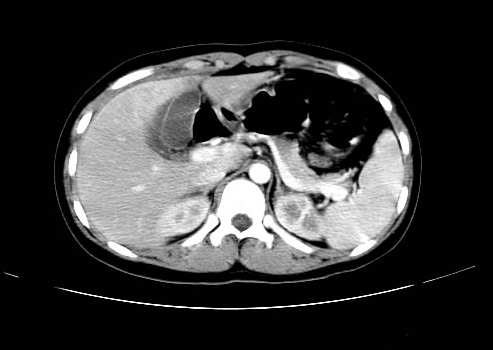

女 16岁  右上腹痛一天,无其他不适

肿块最大径位于十二指肠降段与水平段移行处,并且与肝脏压迹呈“0”形征,可以考虑位于肝外并与胃肠道关系紧密,考虑胃肠道间质瘤(gist)可能较大,须除外神经节起源肿瘤。

肿块与十二指肠关系密切,支持间质瘤诊断.肝脏与结肠均为受压改变.

右下腹巨大肿快,密度不均匀,内见坏死低密度区,边界清楚,与周边胀器明显有分界,未见强化,多考虑来源于间叶组织的良性肿物.

我坚决反对您的观点,该病例定位:横结肠肝曲与升结肠之间的肠系膜及部分肠壁。请看下图:

病灶巨大,少部分向肠腔内生长,大部分向长腔外生长。其密度不均匀,增强显示明显不均匀强化,并见有大片状始终不强化的不规则坏死液化区。虽然病灶中上部形态尚可,病人又如此年轻,但中下部形态、密度、强化特点强烈提示为恶性病灶。综上,我考虑本病例为:恶性胃肠道间质瘤。